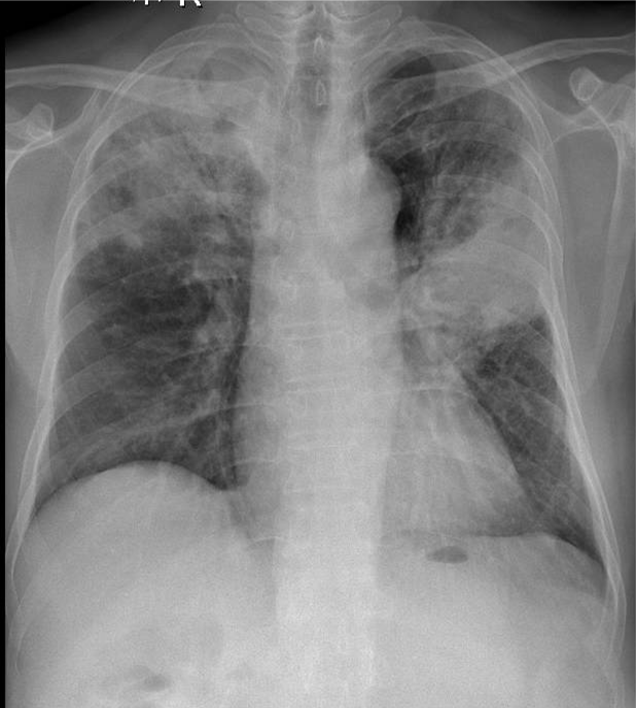

Hãy phân tích tình huống NỮ 73 tuổi -CĐ: LAO PHỔI

1-Tổn thương phế nang lan tỏa thùy trên hai phổi => Viêm phổi